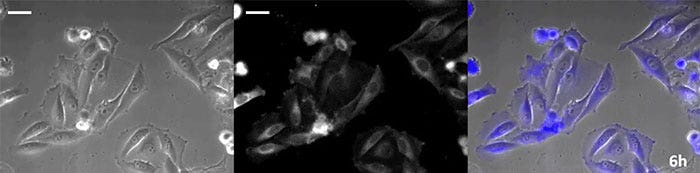

La luciférine de type coelenterazine a une luminosité particulièrement élevée, mais, comme elle s’oxyde assez rapidement dans la cellule, il est nécessaire d’en ajouter régulièrement lors des observations de longue durée. Pour résoudre ce problème, nous avons perfusé des cellules exprimant une protéine luminescente de haute intensité avec du milieu de culture tandis qu’un dispositif d’ajout de substrat automatisé ajoutait automatiquement de la coelentérazine afin que la luminescence puisse être suivie en continu. Nous avons ainsi réussi à suivre les effets d’un médicament en prenant des images de la luminescence en combinaison avec des images en contraste de phase pendant plus de 24 heures (figure 4).

0 heure

Figure 4-1 0 heure

6 heures

Figure 4-2 6 heures